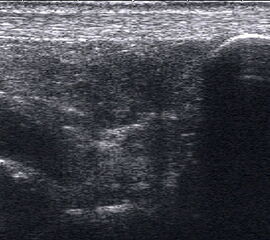

Dorsaler TS hinter dem Innenknöchel.

Abbildung 46

Lagerung: Rückenlage, Außendrehung des Beines.

Schnittführung: TS und LS hinter dem Innenknöchel beginnen und bis zum Os cuneiforme mediale fortführen.

Referenzstrukturen: Innenknöchel, Talus, Os naviculare, Os cuneiforme mediale, Sehnen der Mm tibialis posterior, flexor hallucis longus, flexor digitorum.

Befunde: Häufig betreffen die Pathologen die Tibialis-posterior-Sehne, die als erste Sehne hinter dem Innenknöchel zur Darstellung kommt. Halo-Phänomen und echoarme Verdickung bei akuter Tendinopathie, zunehmend inhomogen und echogen mit Kaliberschwankungen bis hin zu Teilrupturen bei Chronifizierung 5. Für die Erkennung von Teilrupturen sind TS in verschiedener Höhe besonders wichtig. Bei komplettem Riss mit Retraktion im LS Bild wie Spargelspitze mit umgebender Flüssigkeit oder Hämatom. Ein Os tibiale externum erscheint als echoreiche Struktur im Verlauf der Tibialis posterior Sehne mit dorsaler Schallauslöschung. Ein Os naviculare cornutum imponiert als starke Prominenz im Ansatzbereich der Tibialis posterior Sehne.